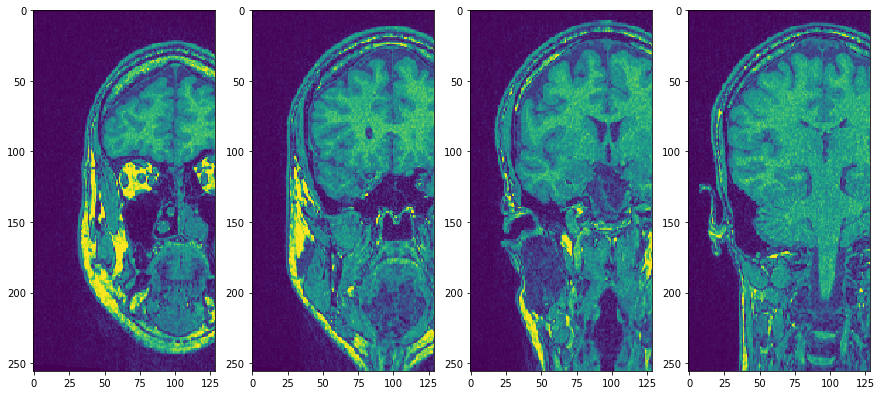

Utilice subplots para ponerlos uno al lado del otro

fig, axs = plt.subplots(1, 4, figsize=(15, 7))

cle.imshow(transposed_image[75], plot=axs[0])

cle.imshow(transposed_image[100], plot=axs[1])

cle.imshow(transposed_image[125], plot=axs[2])

cle.imshow(transposed_image[150], plot=axs[3])

../_images/c7f6aa8ebe01402e92cd9a40e380bf9cf1b1febdd7a6e15069da4e5756ff6e04.png